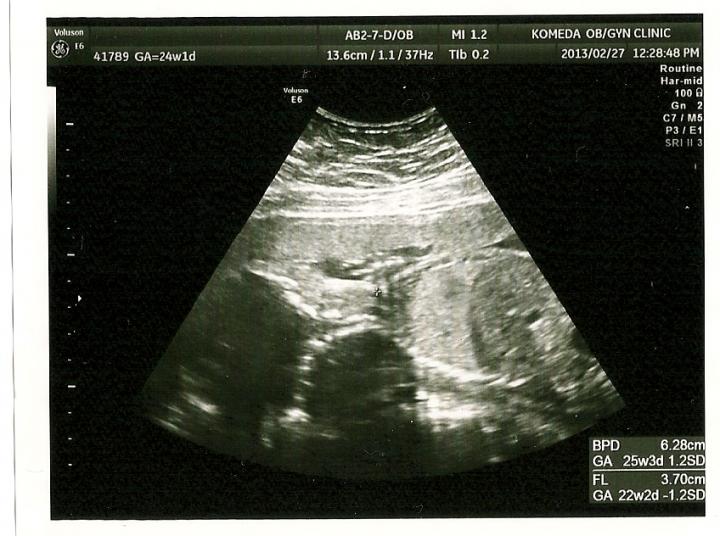

横向きですが・・・

エコーで見ているときは 説明してくれるのでわかるのですが、写真を貰うと

『??????????????』

でも しっかり成長していました(^^)

しか~し 逆子 でしたので 性別は 次ってことになりました(^^)

まだ 24週ですので 逆子は気にならなかったのですが、性別が気になって仕方がありません(><)